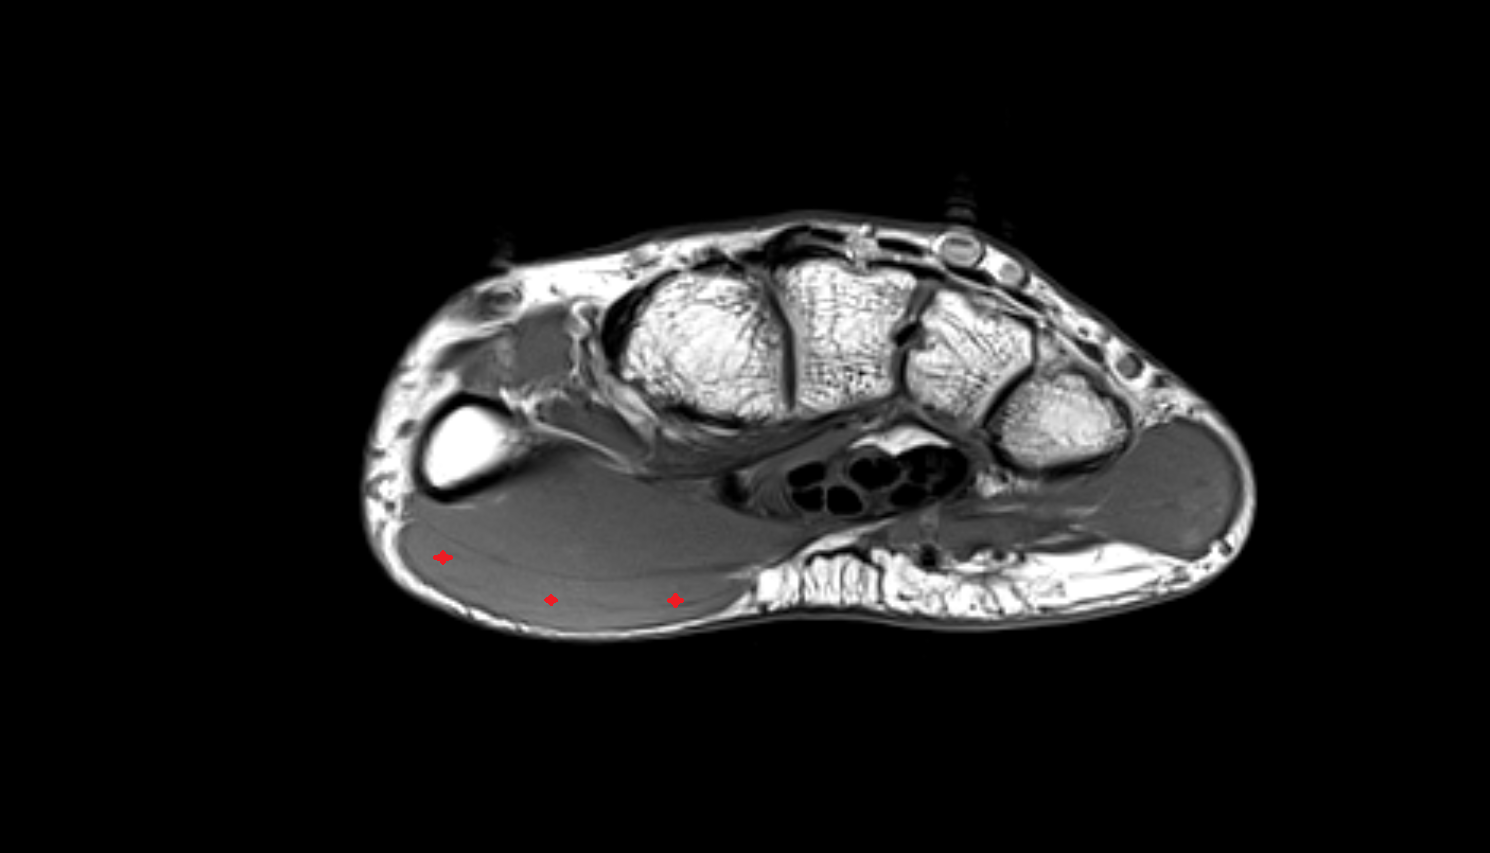

- Plantar aponeurosis